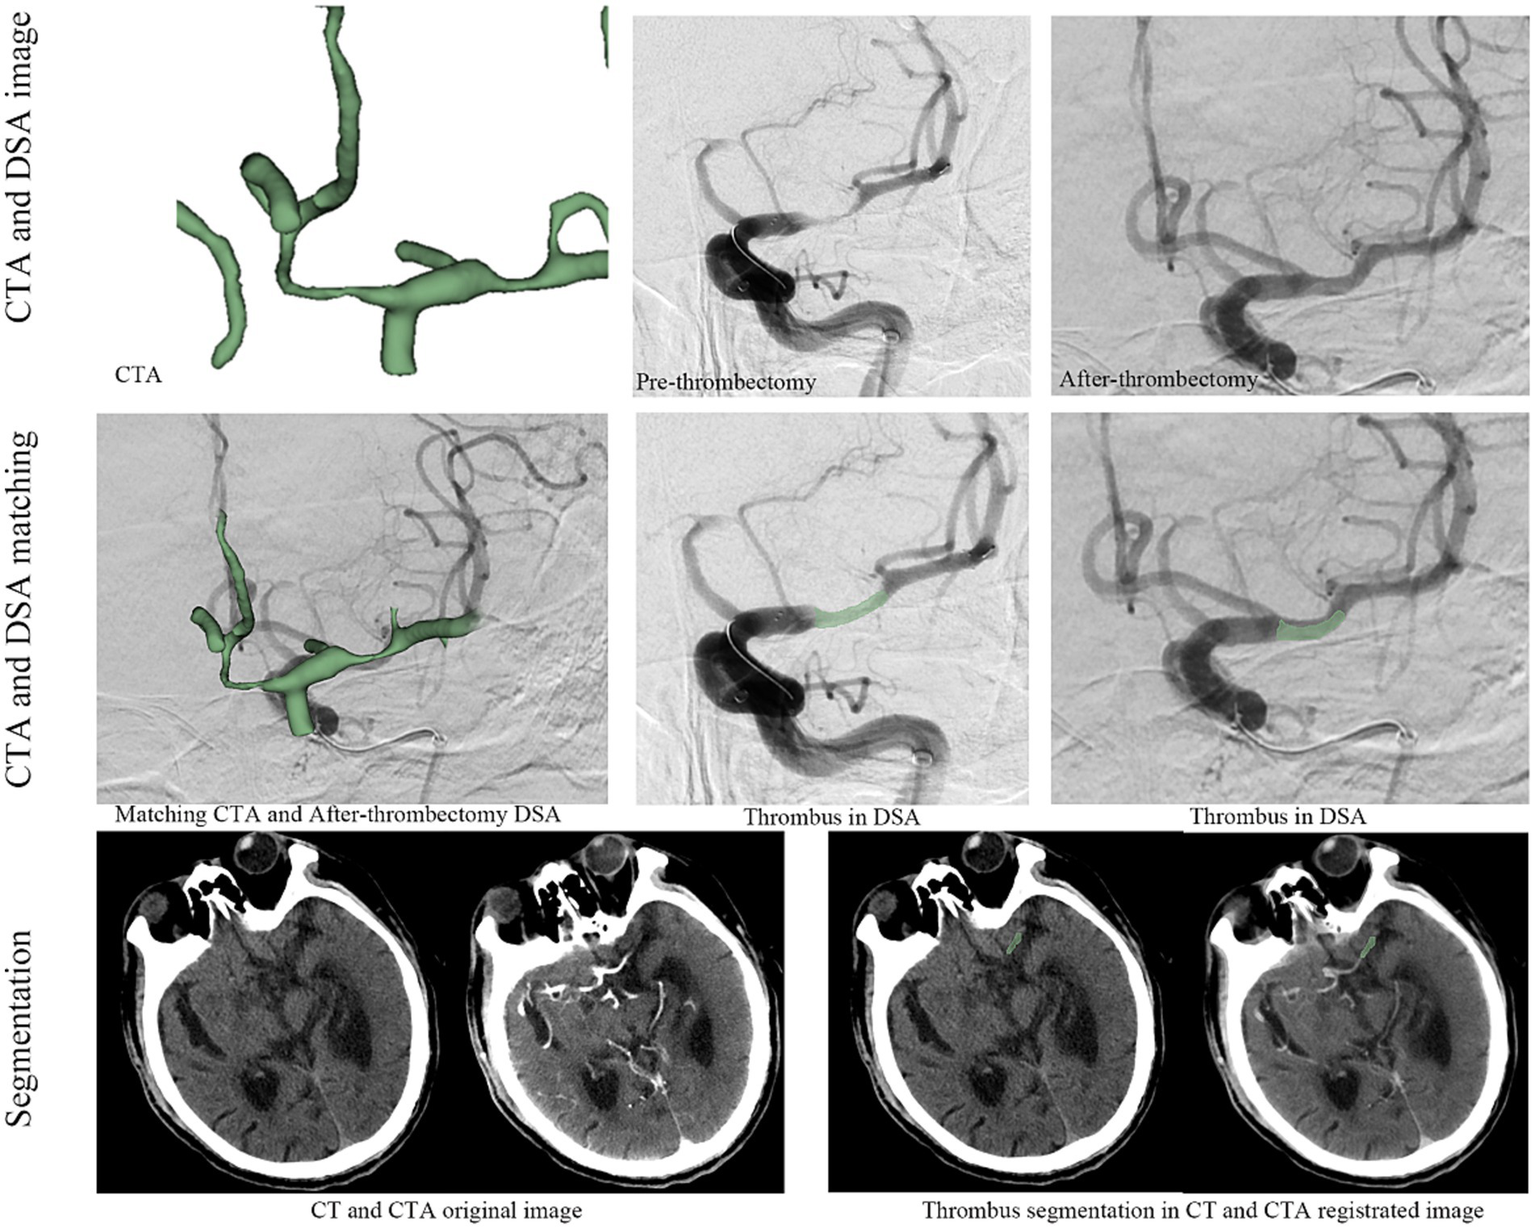

CT and CTA images were obtained using 64-slice, 128-row CT scans (Siemens, Germany) with a slice thickness of 0.5 mm. Preoperative CTA images were matched to postoperative DSA images using ANTS software to accurately identify the thrombus (Figure 1). Thrombus segmentation was performed based on the matching results of CTA and postoperative DSA; the location of the thrombus was annotated using NCCT and CTA (Figure 1). Segmentation was conducted by two experienced clinicians using 3D Slicer (version 4.9.0, National Institutes of Health) with verification by another senior physician. Appropriate measures were taken to minimise patient discomfort during the procedures. Following thrombus segmentation, Python (version 2.7.13) was used to automatically segment the perithrombus areas within a 1 mm boundary. Additionally, researchers were blinded to the patients’ clinical information.

Figure 1

The workflow for thrombus radiomics feature extraction.